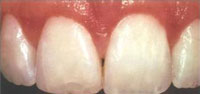

• Gingivitis: Early stage with inflammation and bleeding gums